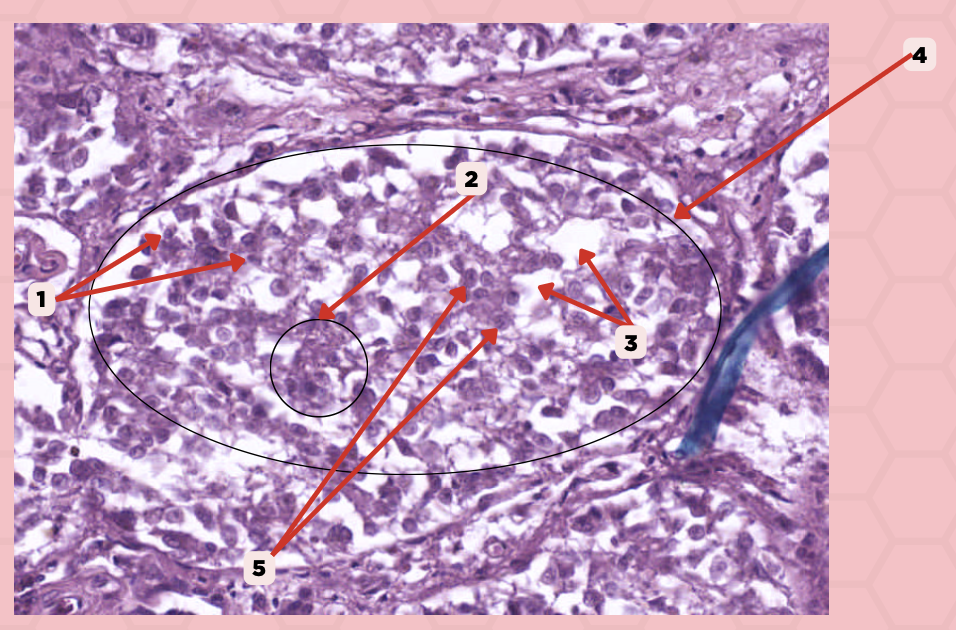

Identify the specimen.

Lobule

Identify the structure labeled as 1.

#5 Pinealocytes (Chief Cells)

Which among these structures are modified neurons that are responsible for synthesizing melatonin?

#1 Interstitial Cells

Which among these are supporting cells that are morphologically similar to astrocytes?

Interstitial Cells

Identify the structure labeled as 1.

Clusters (Cords) of Cells

Identify the structure labeled as 2.

Capillaries

Identify the structure labeled as 3.

Lobule

Identify the structure labeled as 4.

Pinealocyte

Identify the structure labeled as 5.